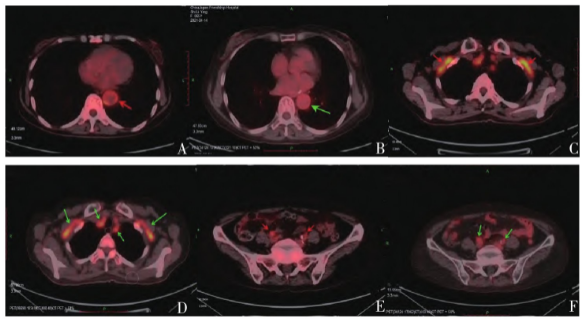

患者拒绝行动脉活检,18F-脱氧葡萄糖

正电子发射断层扫描(18F-deoxyglucose positron emission tomography,18F-FDG-PET/CT)示主动脉、双侧头臂动脉-锁骨下动脉-肱动脉、髂动脉及股动脉上段管壁弥漫性增厚,不均匀葡萄糖代谢增高(图2A、3A、3E),腰2-5双侧椎小关节、双侧坐骨结节周围及双髋关节周围软组织代谢异常增加(图3C、3E)。确诊为巨细胞动脉炎(giant cell arteritis,GCA),予醋酸泼尼松片(60mg,qd)治疗3d,患者乏力等症状明显改善。

2021年4月6日复查,查体见满月脸;白细胞5.11×109/L,C反应蛋白0.398mg/dl,ESR 11mm/h,Ig M26.1mg/dl;肝肾功能正常;血管超声(图1C、1D)示颞动脉“晕环征”消失;18F-FDG-PET/CT示:主动脉、双侧头臂动脉-锁骨下动脉-肱动脉、髂动脉及股动脉上段代谢较前减低(图2B),腰2-5双侧椎小关节代谢增高区消失,双侧坐骨结节及双髋关节周围软组织代谢减低,颈6椎体左侧局部高代谢消失(图2B、3B、3D、3F)。患者症状明显好转,食欲佳,体重增加约5kg。继续予醋酸泼尼松龙片(15mg,qd)口服治疗,每2周减少2.5mg。患者后未诉明显不适,规律复诊。

图3 患者治疗前后18F-FDG-PET/CT影像(横断面)。A、C、E为治疗前表现,可见腰2-5双侧椎小关节周围软组代谢异常增加,主动脉、双侧坐骨结节周围及双髋关节周围软组织、髂动脉上段管壁不均匀葡萄糖代谢增高;B、D、F为治疗后表现,上述部位代谢增高区消失或代谢较前减低。